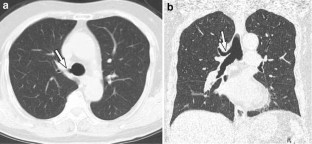

Fig. 4